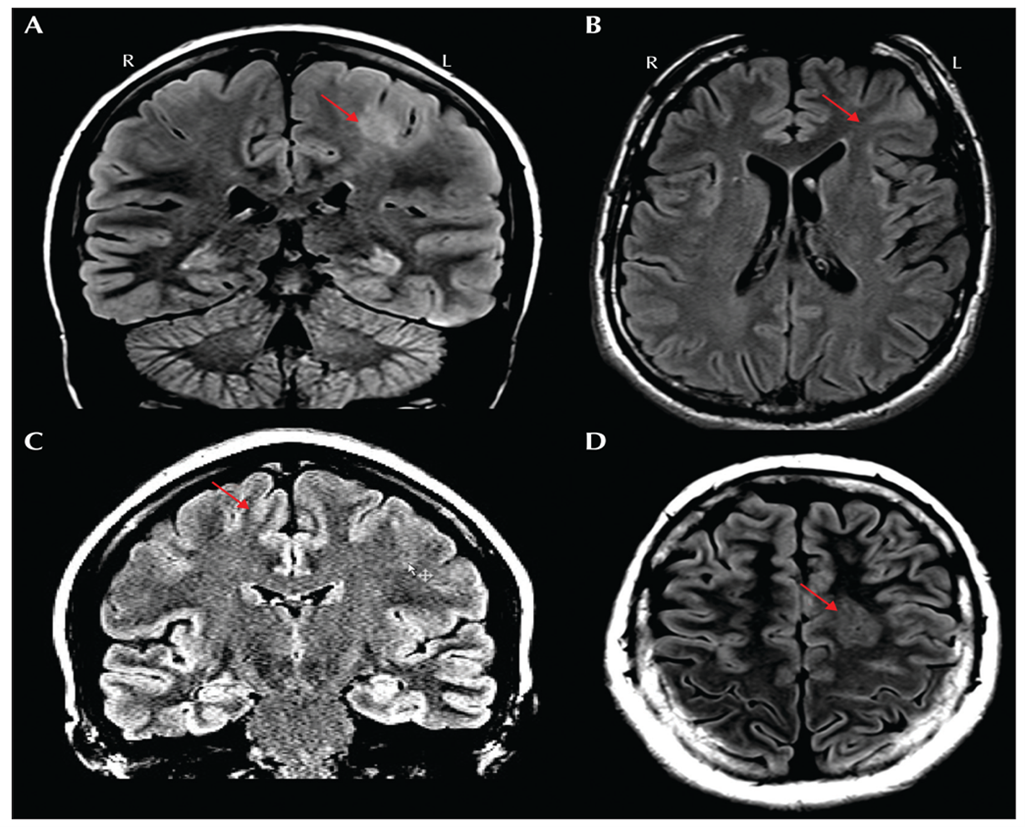

MRI features of FCD II are subtle but critical for diagnosis as Figure 4 demonstrates.

- Transmantle Sign: Funnel-shaped hyperintensity extending from the lateral ventricle to the cortex, most characteristic of FCD IIb.

- Other MRI markers:

- Abnormal cortical thickness

- Blurring of gray-white matter junction

- Signal abnormalities on T1 and T2 sequences

Subtype Examples:

- FCD IIa: Thickened cortex and hyperintensity on T2-weighted FLAIR but lacks balloon cells histologically.

- FCD IIb: Strong transmantle sign and severe cortical thickening.